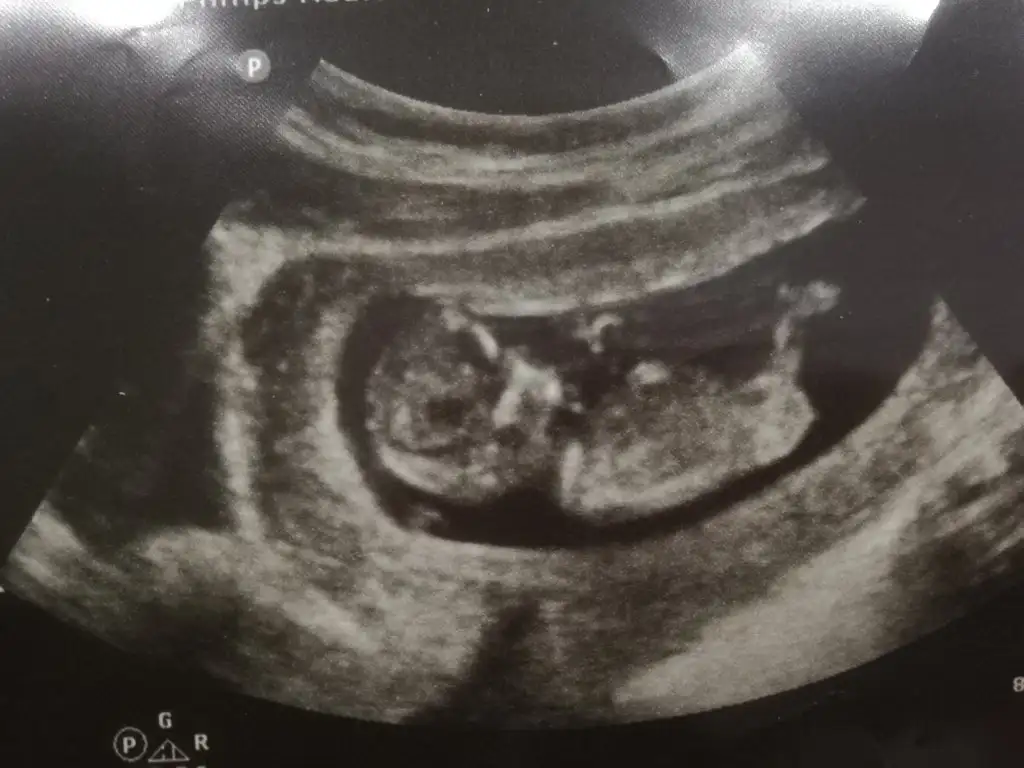

👫 11 yada 12 yada 13 hafta Nub usg nizi konumuza paylaşın

11. Hafta %48

12. Hafta %91

13. Hafta %95 doğruluğu var ☺️